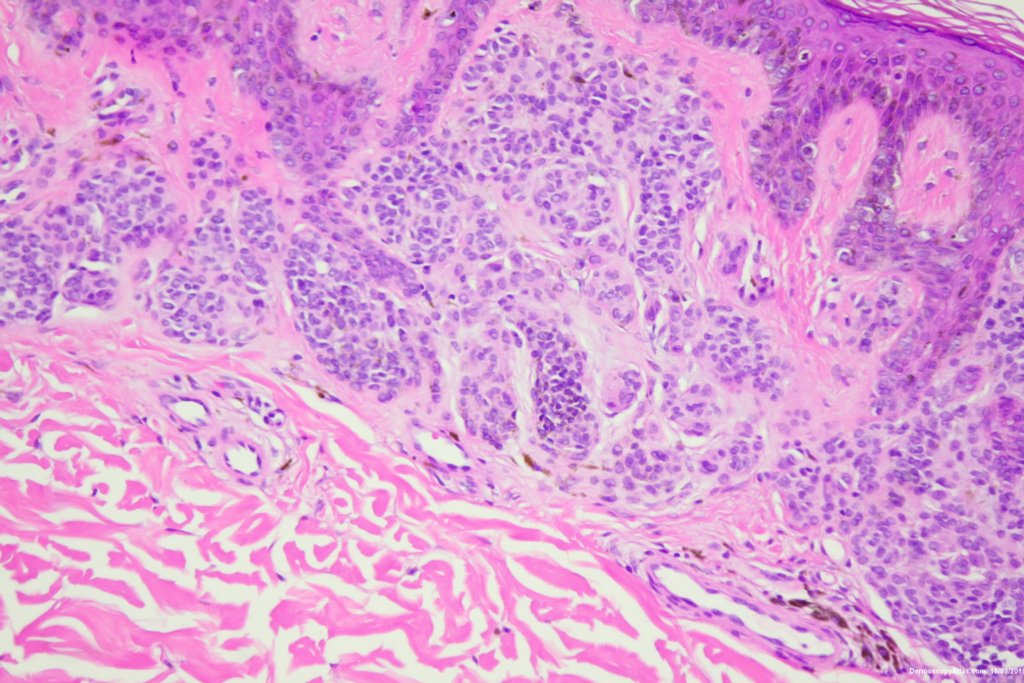

Description: Some grey dots and thickened network

A pigmented lesion on the ankle which showed some grey dots suggesting regression and a slightly thickened network in parts.

Histology showed a compound nevus with some pigment in melanophages in the dermis giving the grey.